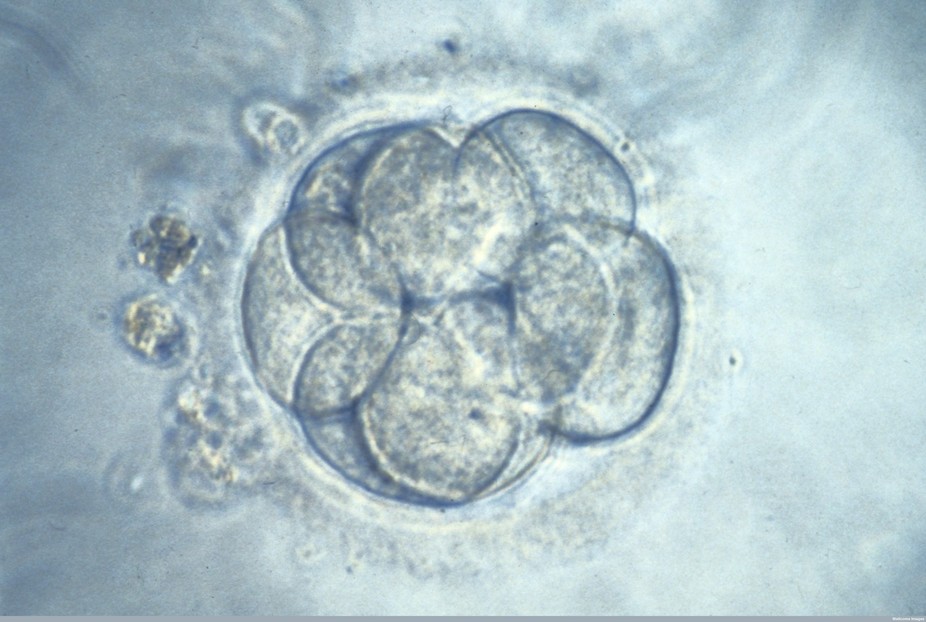

After genome editing, the aim would be for 100% of embryos to be normal. In the first round of the experiments, they found that 66.7% of embryos – 36 out of 54 – were normal after being injected with CRIPSR. Of the remaining 18 embryos, five had remained unchanged, suggesting editing had not worked. In 13 embryos, only a portion of cells had been edited.

The level of efficiency is affected by the type of CRISPR machinery used and, critically, the timing in which it is put into the embryo. The researchers therefore also tried injected the sperm and the CRISPR-Cas9 complex into the egg at the same time, which resulted in more promising results. This was done for 75 mature donated human eggs using a common IVF technique called intracytoplasmic sperm injection. This time, impressively, 72.4% of embryos were normal as a result. The approach also lowered the number of embryos containing a mixture of edited and unedited cells (these embryos are called mosaics).

Finally, the team injected a further 22 embryos which were grown into blastocyst – a later stage of embryo development. These were sequenced and the researchers found that the editing had indeed worked. Importantly, they could show that the level of off-target mutations was low.